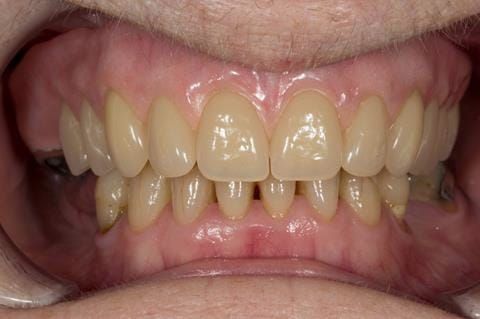

- Poorly fitting cobalt chromium based maxillary partial denture, which has been added to. This exhibited poor retention, stability and tissue fit (support). Unable to wear a new acrylic based denture.

- Eight mandibular anterior teeth worn incisal edges from now extracted maxillary anterior crowns. Gingivitis - owing to inadequate oral hygiene.

Following consultation and second discussion appointment the patient chose to have option 2 namely, a window denture - maxillary cobalt chromium based partial denture. The clinical situation and treatment process is shown in detail below with photographs. The patient was successfully rehabilitated with this and her quality of life considerably improved. The clinical work was provided by Finlay and the technical work by Rowan.